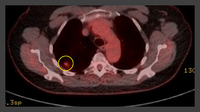

PET CT scan with 18-fluorodeoxyglucose (18-FDG) showing a high uptake peripheral left lung lesion. Surgical resection confirmed a moderately differentiated squamous cell lung cancer

From the collection of Dr George Tsaknis, MD, PhD, FRCP(London), MRQA, MAcadMEd, PGCert; used with permission